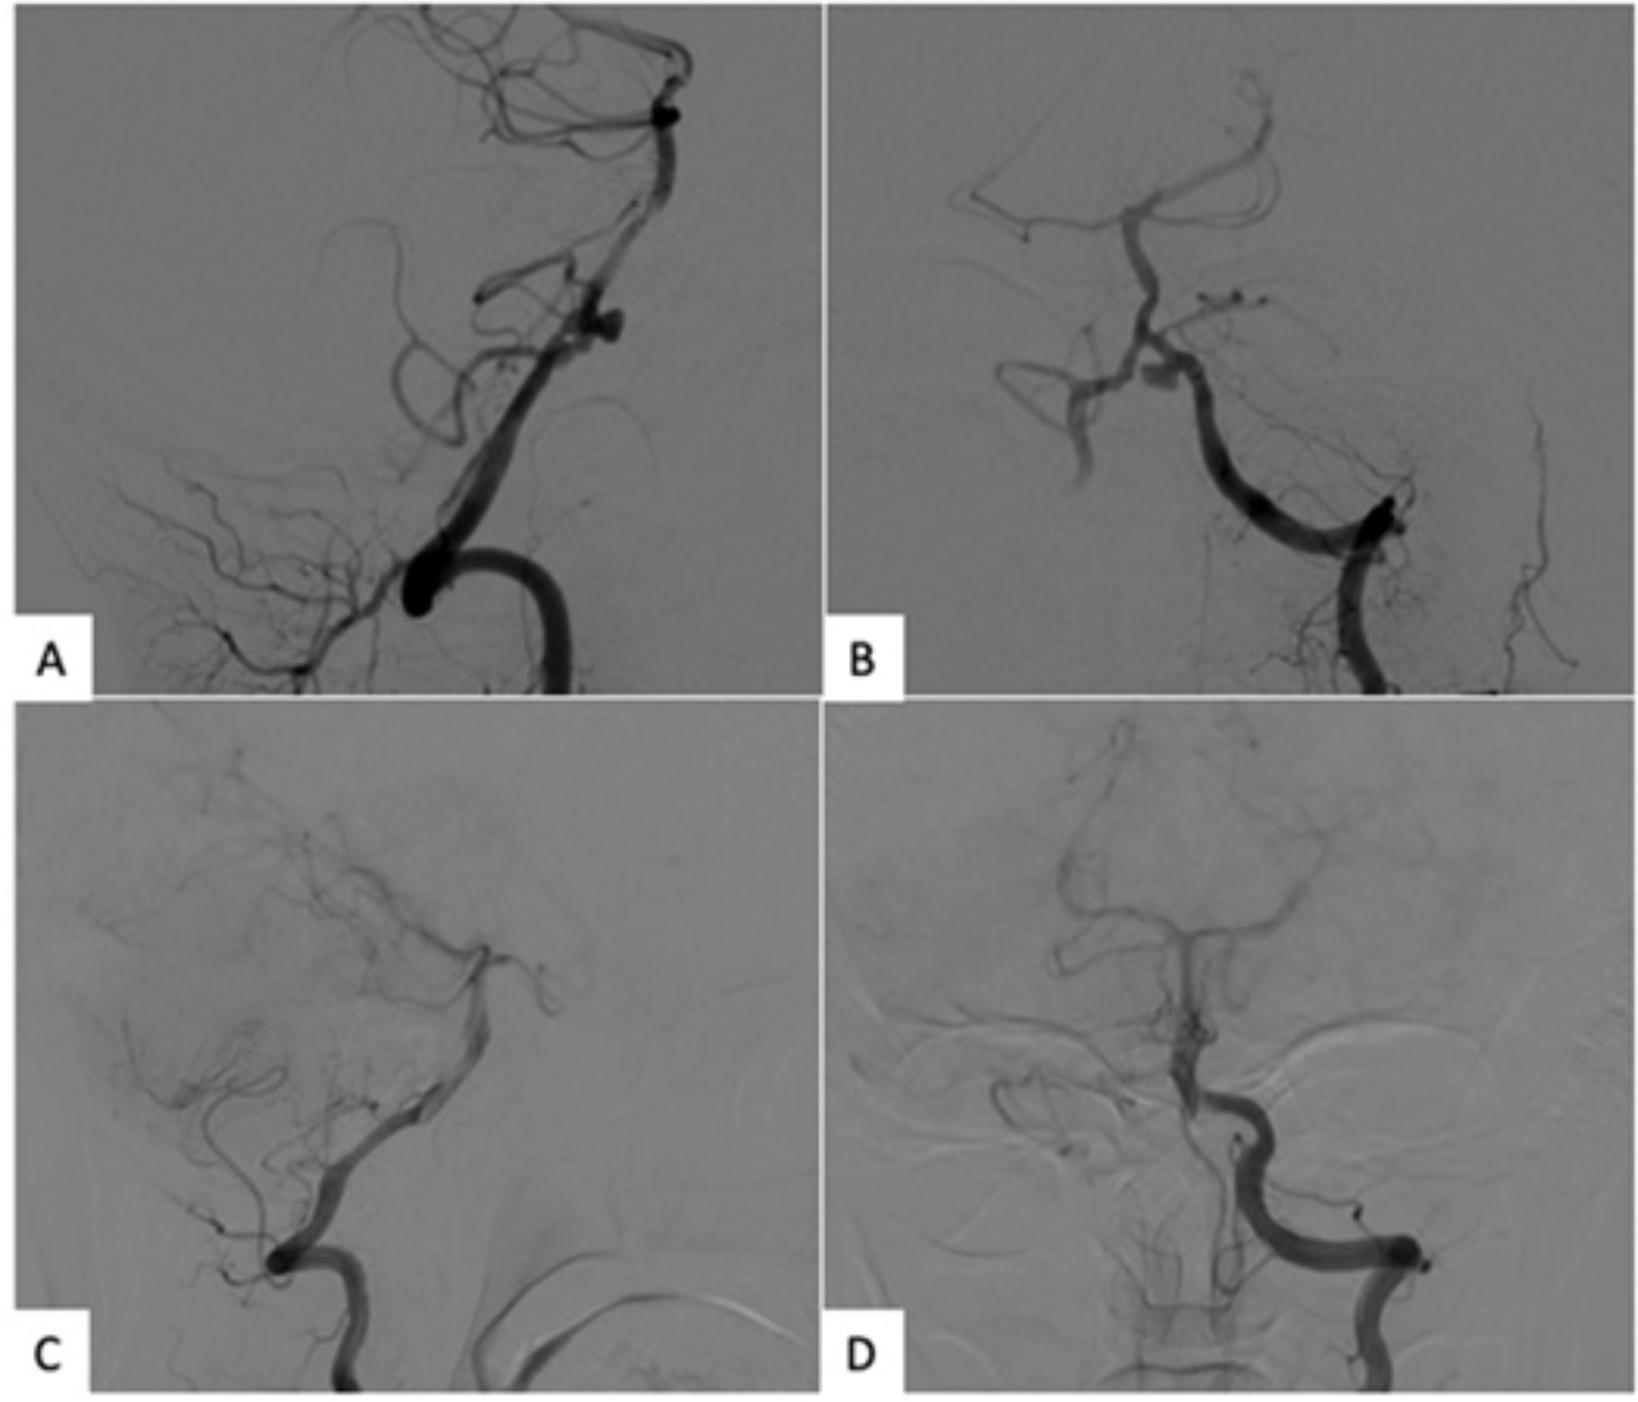

Abstract Image